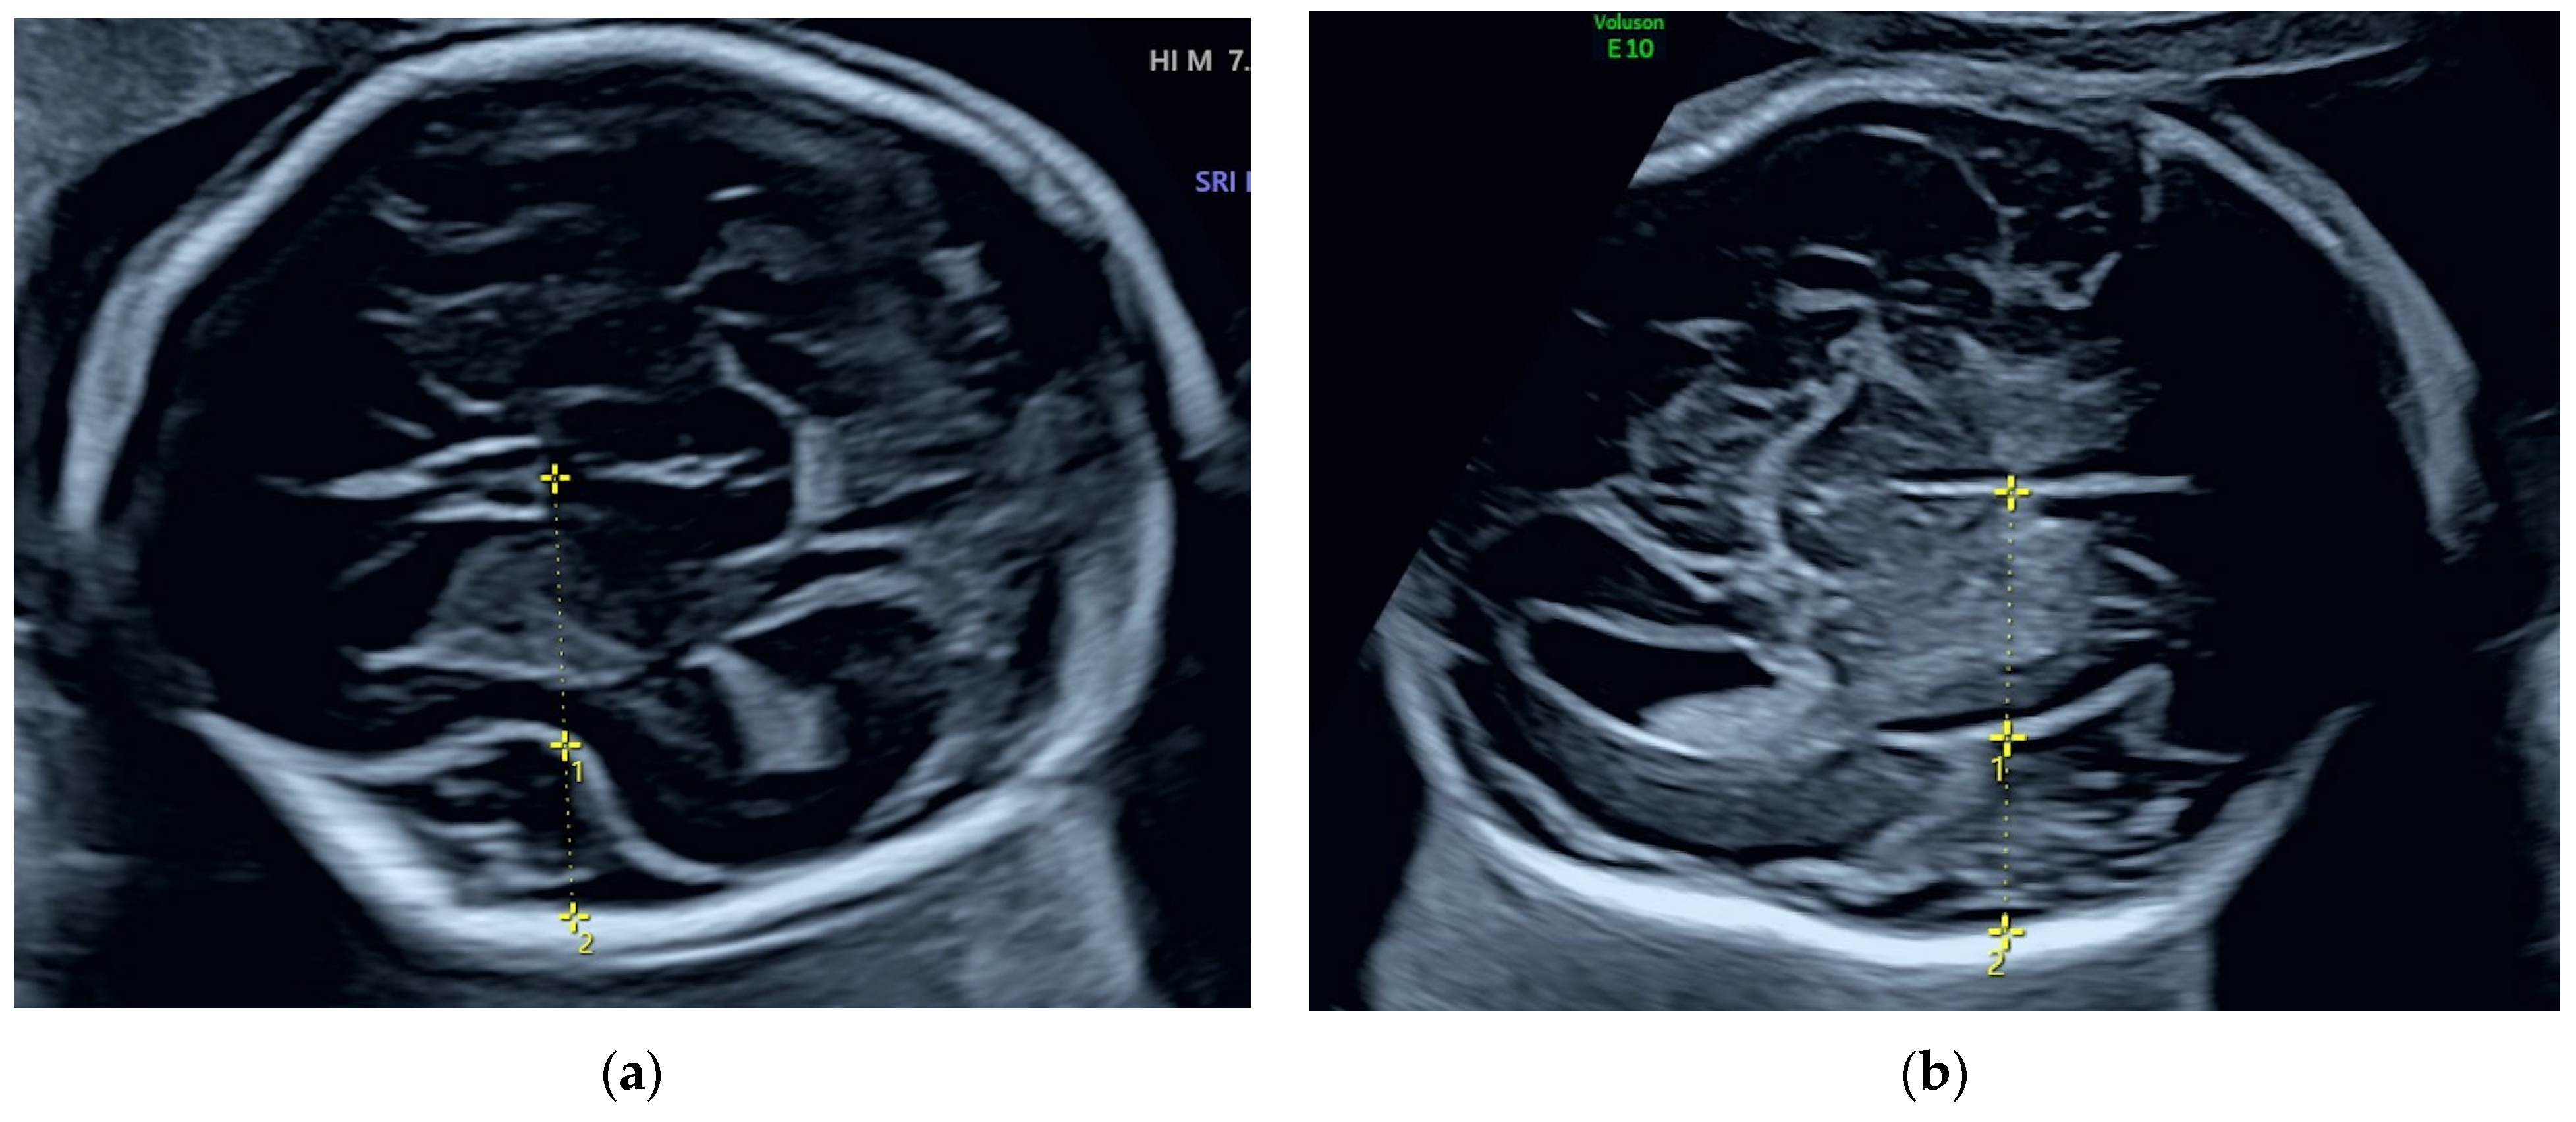

2.1.2. Ultrasound Findings

2.2.2. Ultrasound Findings